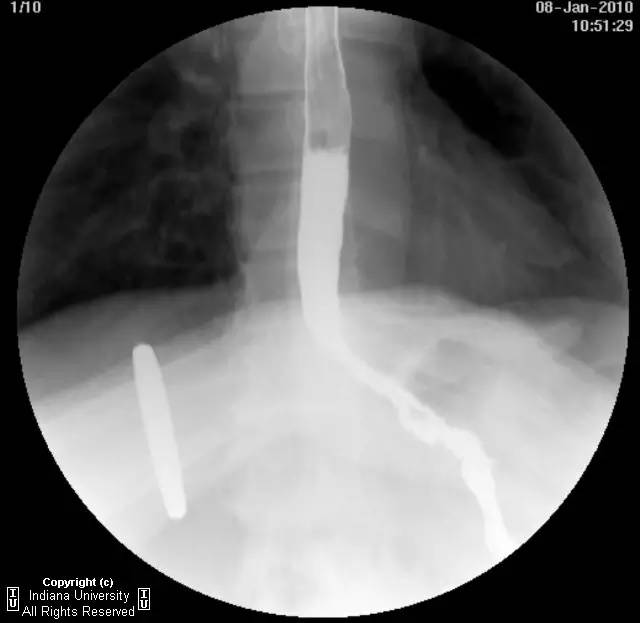

【影像学表现】下咽部正常,环咽肌功能正常。颈段食管无外生性病变压迫或异常扩张。胸中段食管长节段狭窄,逐渐移行为正常食管粘膜。大量小的烧饼样钡斑位于相应食管外呈浮萍样,与食管管腔无直接交通。稠或稀钡剂通过均无延迟。1cm钡剂片延迟通过,约30分钟后自动溶解。余食管动力正常。

【诊断】食管壁内假性憩室并长节段狭窄

Long segmentstricture with esophageal intramural pseudodiverticulosis